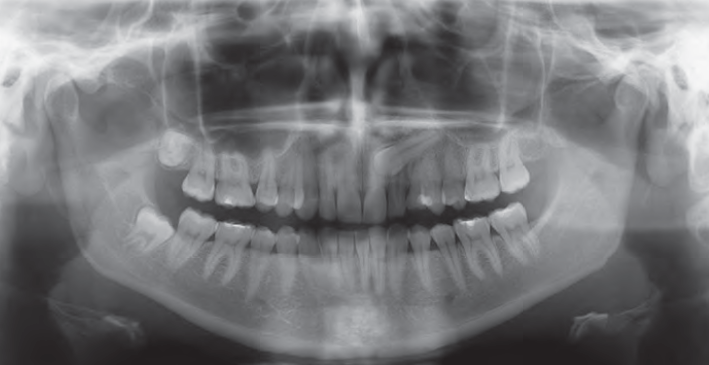

Along with the ability to transform from 2D Panoramics to Cephalometrics to 3D, the GXDP-700 Series gives clinicians dependable image capture of a wide variety of radiographs. These images are valuable for diagnosis and treatment planning of caries, root investigation, orthodontics, implants, and other surgical procedures, as well as patient education.

• Pans for general surveys and progress checks during orthodontic treatment

Panoramic

The GXDP-700’s panoramic imaging includes a wide variety of projections, including bitewing and TMJ, to expand your radiographic capabilities. Other projections consist of orthogonals, frontal dentition, and sinus, and most views also allow for the selection of either right or left exposures.